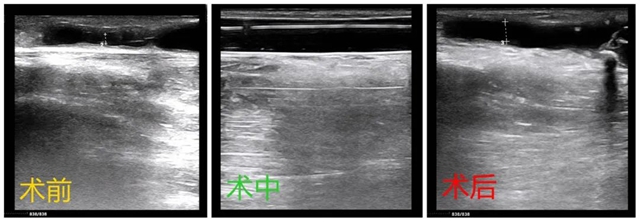

超声引导/DSA下经皮腔内血管成形术(PTA)目前被广泛地应用于解决尿毒症血液透析患者内瘘狭窄、闭塞等问题。

经皮腔内血管成形术采用的是同轴扩张血管的原理,从已插入并通过瘘静脉狭窄处一根带有囊袋的导管,将囊袋膨胀至一适度压力,从而增大管腔直径。技术成功与否可以从术后血管造影确认。

介入治疗在血管通路并发症的治疗中具有独特的优势。对于血管通路初期发生狭窄失功时,初始治疗方案大多以经皮腔内血管成形术为主,如果此术失败或狭窄频繁复发时可考虑支架植入术。另外,肾友需建立早期监测机制,及时发现相关并发症,适时干预,并对各种治疗方案进行权衡利弊。